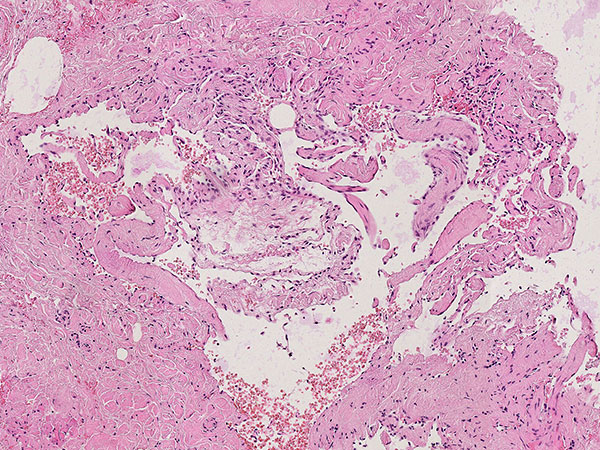

Hematoxylin & eosin stain, 64x magnification: Layered, predominantly connective tissue appearance of the older, partially organized phlebolith. The phlebolith is surrounded by multiple proliferated, irregularly structured, thin-walled vascular spaces.